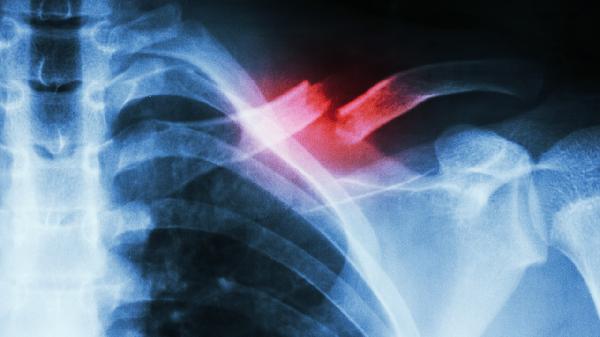

如颌骨囊肿患者的病情过于严重,宜采用肿瘤刮除术来治疗,注意在手术之前需进行局麻处理,这样才能让患者在无痛的情况下完成手术。如囊肿的范围较大时,往往会因为骨质缺损较多,需要在全麻的情况下从口外进行切口,手术过后需要进行颌间结扎暂时固定,这样才能降低骨折的发生率。当患者出现角化囊肿时,极容易产生恶变,因此在手术时刮除应当彻底,必要时可以进行囊肿外围切除部分骨质。